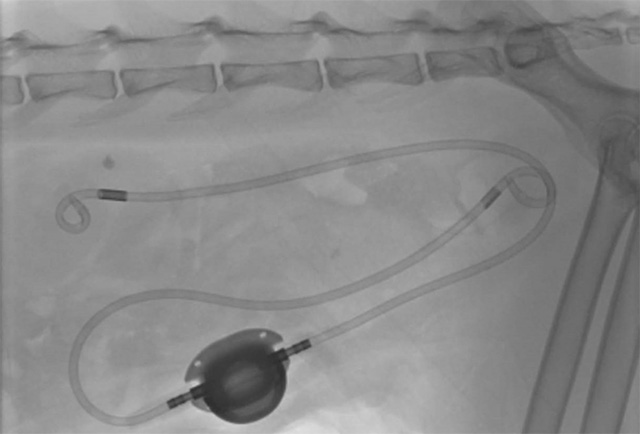

尿は腎臓で作られたのち、尿管⇨膀胱⇨尿道を通って体の外に排泄されます。その通り道に、尿の成分を元にした石が作られるのが尿路結石症で、できる部位により尿管結石・膀胱結石・尿道結石と名前が変わります。この結石は、尿が出なくなったり炎症を起こしたりと様々な悪さをします。治療は、石を溶かす内科治療や溶けない石に対して行う外科治療があります。当院では、これら全てに対して外科治療を行うことができ、またSUBという特殊なステント手術も行うことができます。

尿は腎臓で作られたのち、尿管⇨膀胱⇨尿道を通って体の外に排泄されます。その通り道に、尿の成分を元にした石が作られるのが尿路結石症で、できる部位により尿管結石・膀胱結石・尿道結石と名前が変わります。この結石は、尿が出なくなったり炎症を起こしたりと様々な悪さをします。治療は、結石を溶かす内科治療や溶けない結石に対して行う外科治療があります。当院では、これら全てに対して外科治療を行うことができ、またSUBという特殊なステント手術も行うことができます。

尿管結石や膀胱腫瘍、膀胱結石など腎泌尿器疾患への手術の執刀を数多く経験しています。細かな操作が必要なマイクロサージェリーやSUB設置術などにも対応しています。